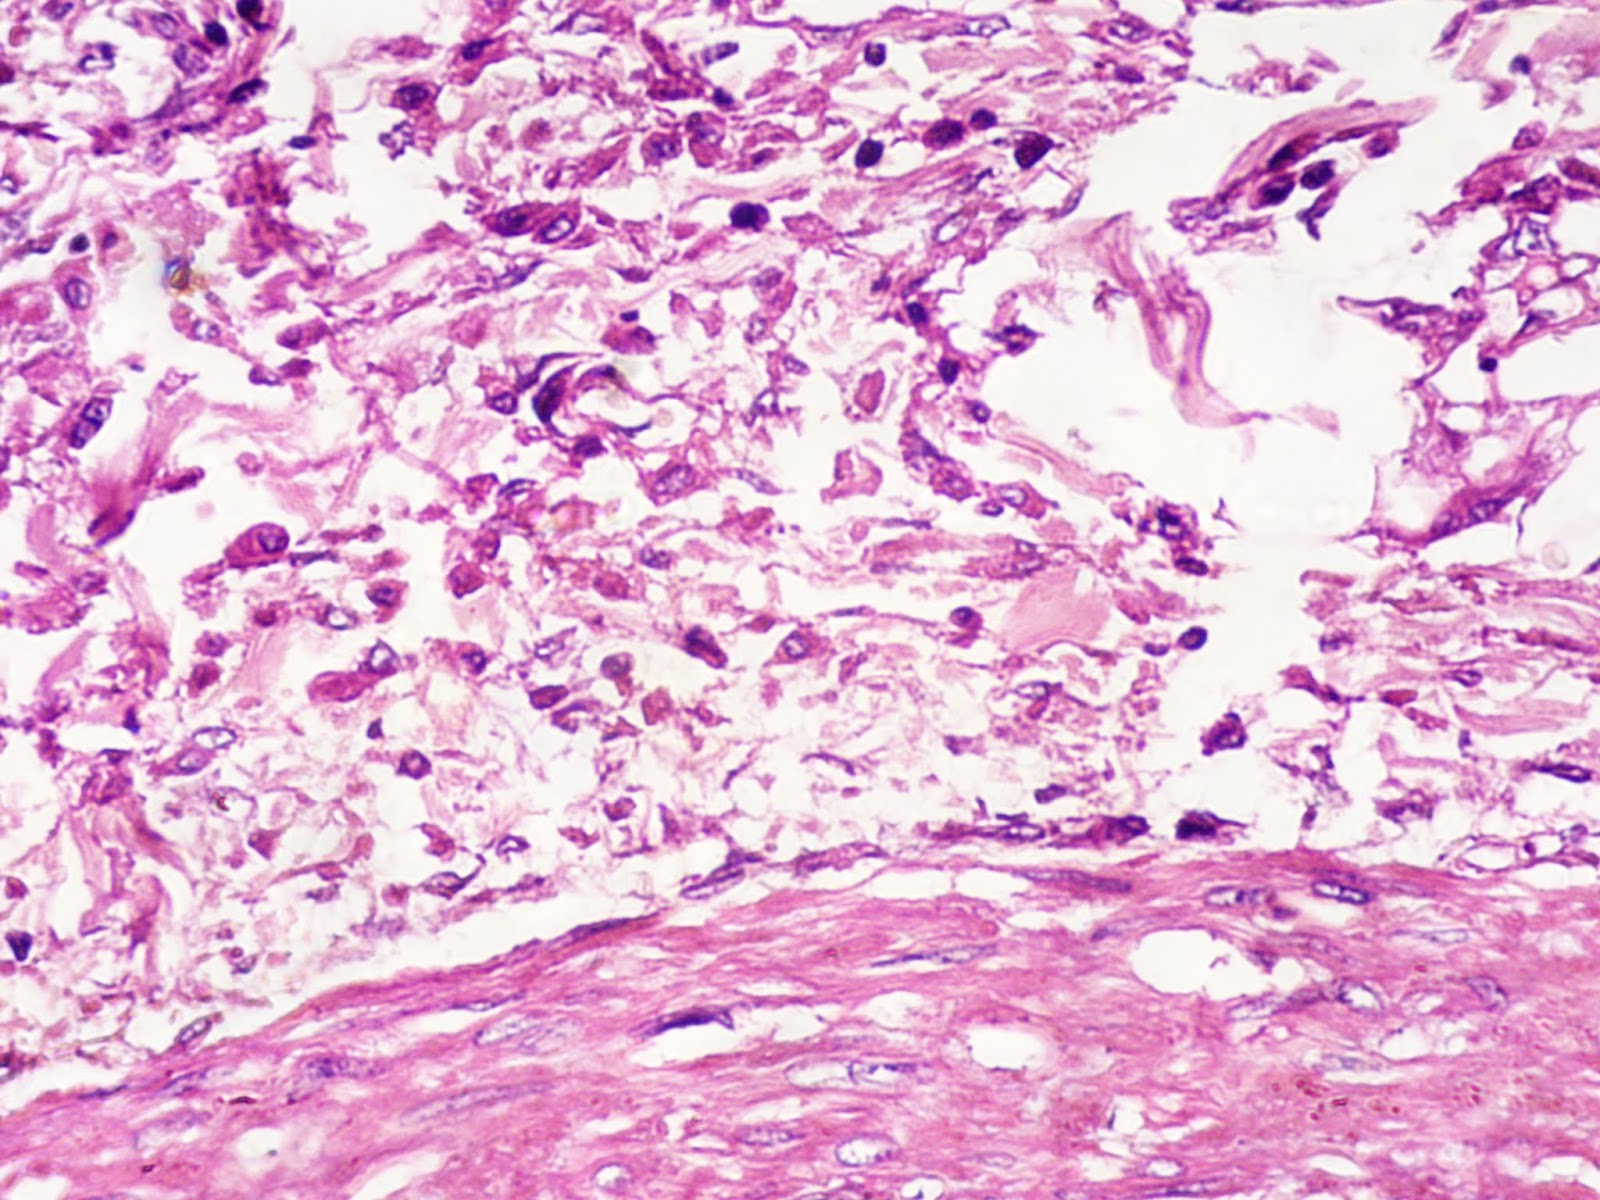

Bread And Butter Pericarditis Means . Pericarditis, also known as “bread and butter” pericarditis.7 in such an entity, the pericardium, which is regularly smooth and bright, becomes. This is another example of fibrinous pericarditis. Pericarditis is the inflammatory process involving the pericardium as a result of a systemic disease or a primary pericardium. There are a number of possible causes of acute fibrinous pericarditis,. The cause in this case is unknown. This is an example of acute fibrinous (bread and butter) pericarditis. The epicardial surface of the heart shows a shaggy fibrinous exudate.

Pericarditis, also known as “bread and butter” pericarditis.7 in such an entity, the pericardium, which is regularly smooth and bright, becomes. This is another example of fibrinous pericarditis. The epicardial surface of the heart shows a shaggy fibrinous exudate. The cause in this case is unknown. This is an example of acute fibrinous (bread and butter) pericarditis. Pericarditis is the inflammatory process involving the pericardium as a result of a systemic disease or a primary pericardium. There are a number of possible causes of acute fibrinous pericarditis,.